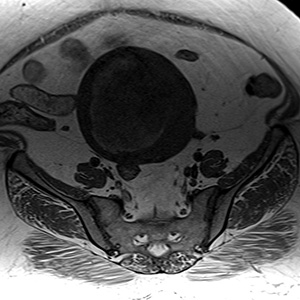

Aksiyel Tl; uterus korpusta heterojen hipointens kitle, içerisinde hiperintens hemoraji alanları mevcut.Aksiyel ve sagital T2; kitle heterojen myometrium ile izointens, içerisinde hiperintens nekroz alanları, endometrial kavite kitle posterioru nda izleniyor.Kontrastlı FS Tl; çoğunluğu kistik nekrotik, kontrast tutan solid alanlar mevcut.

Uterus sarkomu 18-95 yaşları arasında görülebilir ancak 50-60 yaşlarında pik yapar. 60-70 hasta postmenapozal gruptadır. Genellikle heterojen, düzensiz sınırlı, uterusu büyüten kitle şeklindedir. MR' da; T1A hipo-izointens, hiperintens hemoraji odakları görülür. T2A myom etriuma göre izointens, hiperintens nekrotik alanlar izlenir. T1 Kontrastlı görüntü lerde myom etriuma göre daha az kontrastlan an, heterojen kontrast tutan kitle şeklinde izlenir. BT'de; Sınırları uterustan net ayırt edilemeyen, myom etriuma göre hipod ens kitle izlenir. Hiperdens hemoraji alanları görülebilir. IVKM sonrası hipodens nekroz alanları izlenebilir.